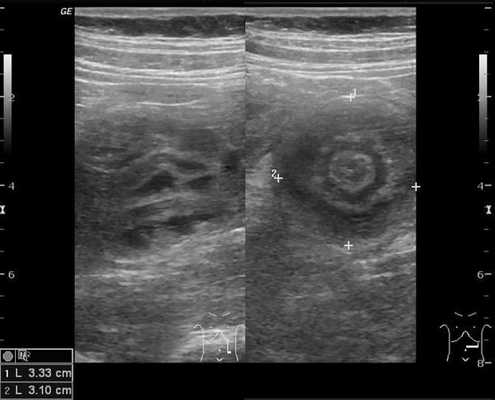

В момент УЗ-исследования врач может определить один из симптомов:

- симптом мишени (за счёт внедрения одной кишки в другую инвагинат на срезе выглядит как мишень);

- симптом "почки с завоздушенным центром".

Комментарии: основным методом в дополнительной диагностике инвагинации кишечника является УЗИ органов брюшной полости. Этот метод обладает 100-процентной диагностической достоверностью и специфичностью в отношении инвагинации кишечника. УЗ-признаками инвагинации кишечника является обнаружение симптома «мишени» или «псевдопочки». Симптом «мишени» заключается в наличии на поперечном срезе двух колец низкой эхоплотности, разделенных гиперэхогенным кольцом. Симптом «псевдопочки» виден на продольном срезе и представляет собой наслаивающиеся друг на друга гипер- и гипоэхогенные слои.